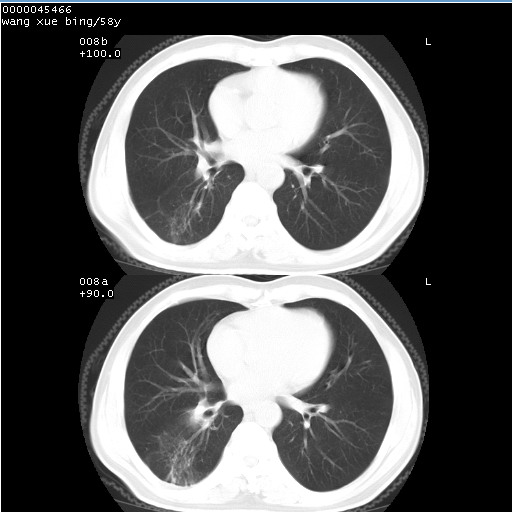

胸部ct轴位平扫(层厚10mm,螺距1.5,重建间隔10mm),图像如下:

右肺下叶团块及不规则空洞,内壁不规则,外缘见粗长毛刺,临近胸膜明显增厚并与病灶关系密切。支持考虑:右肺肺脓肿!建议穿刺病理检查待除外周围型肺癌!

右肺下叶见不规则厚壁空洞,内壁不规则,外缘见粗长毛刺,临近胸膜明显增厚并与病灶关系密切。支持考虑:周围型肺癌!

右肺下叶周围型肺癌伴空洞形成!征象比较明显!分叶、毛刺、胸膜凹陷征、厚壁空洞,壁结节!

空洞壁厚,不规则,其内可见壁结节,周围可见毛刺及阻塞性炎变,多考虑癌性病变.